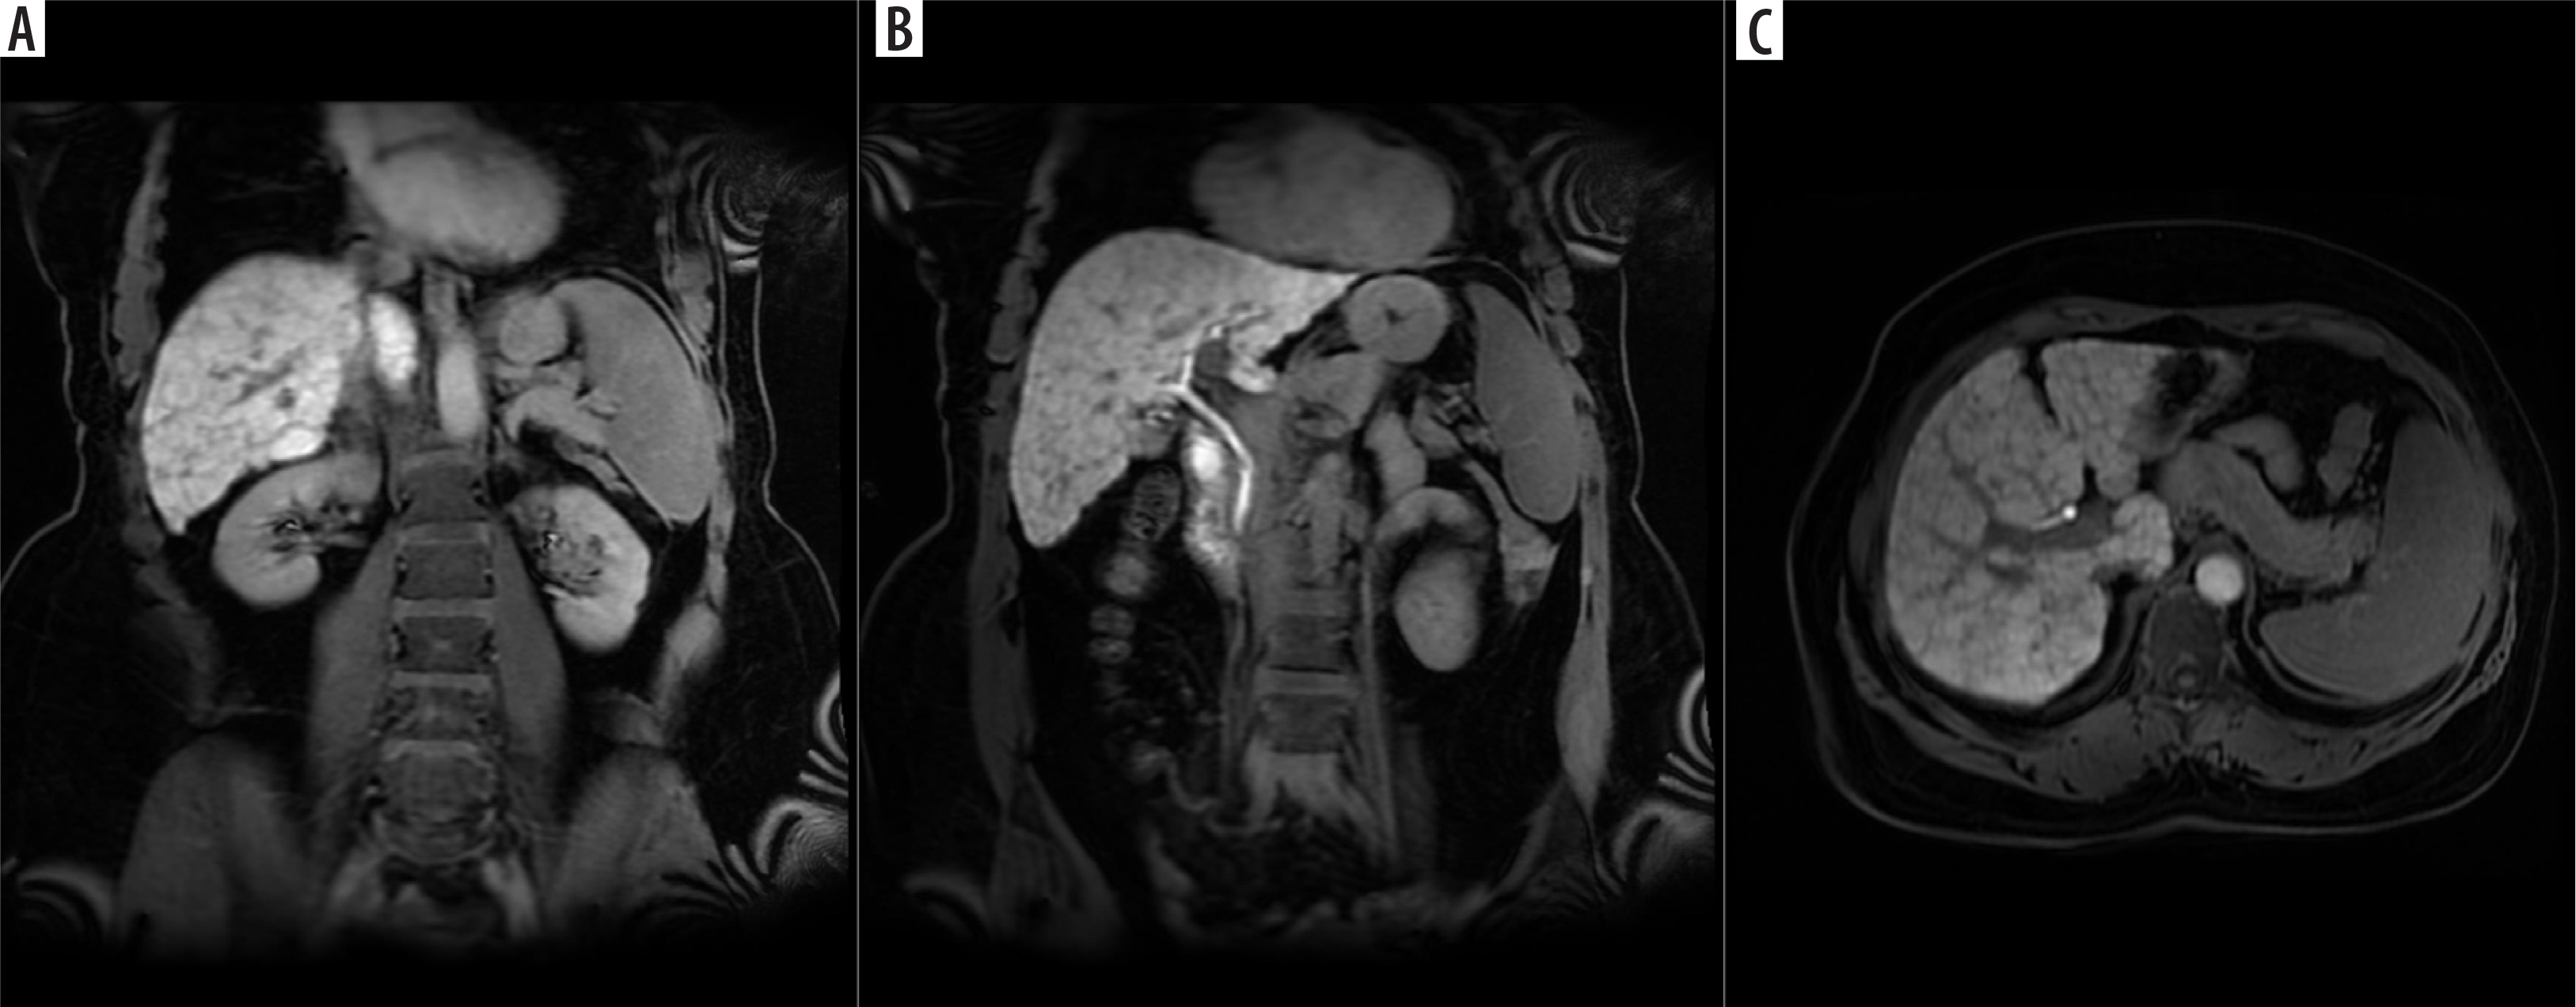

Figure 1

A) Coronal hepatobiliary phase (at 20th min) contrast-enhanced T1AG according to liver parenchyma signal intensity (2 points). B) Coronal hepatobiliary phase (at 20th min) contrast-enhanced T1AG according to biliary excretion (2 points). C) Axial hepatobiliary phase (at 20th min) contrast-enhanced T1AG according to portal vein signal intensity (2 points). The FLIS score is the sum of these points (FLIS score = 6)